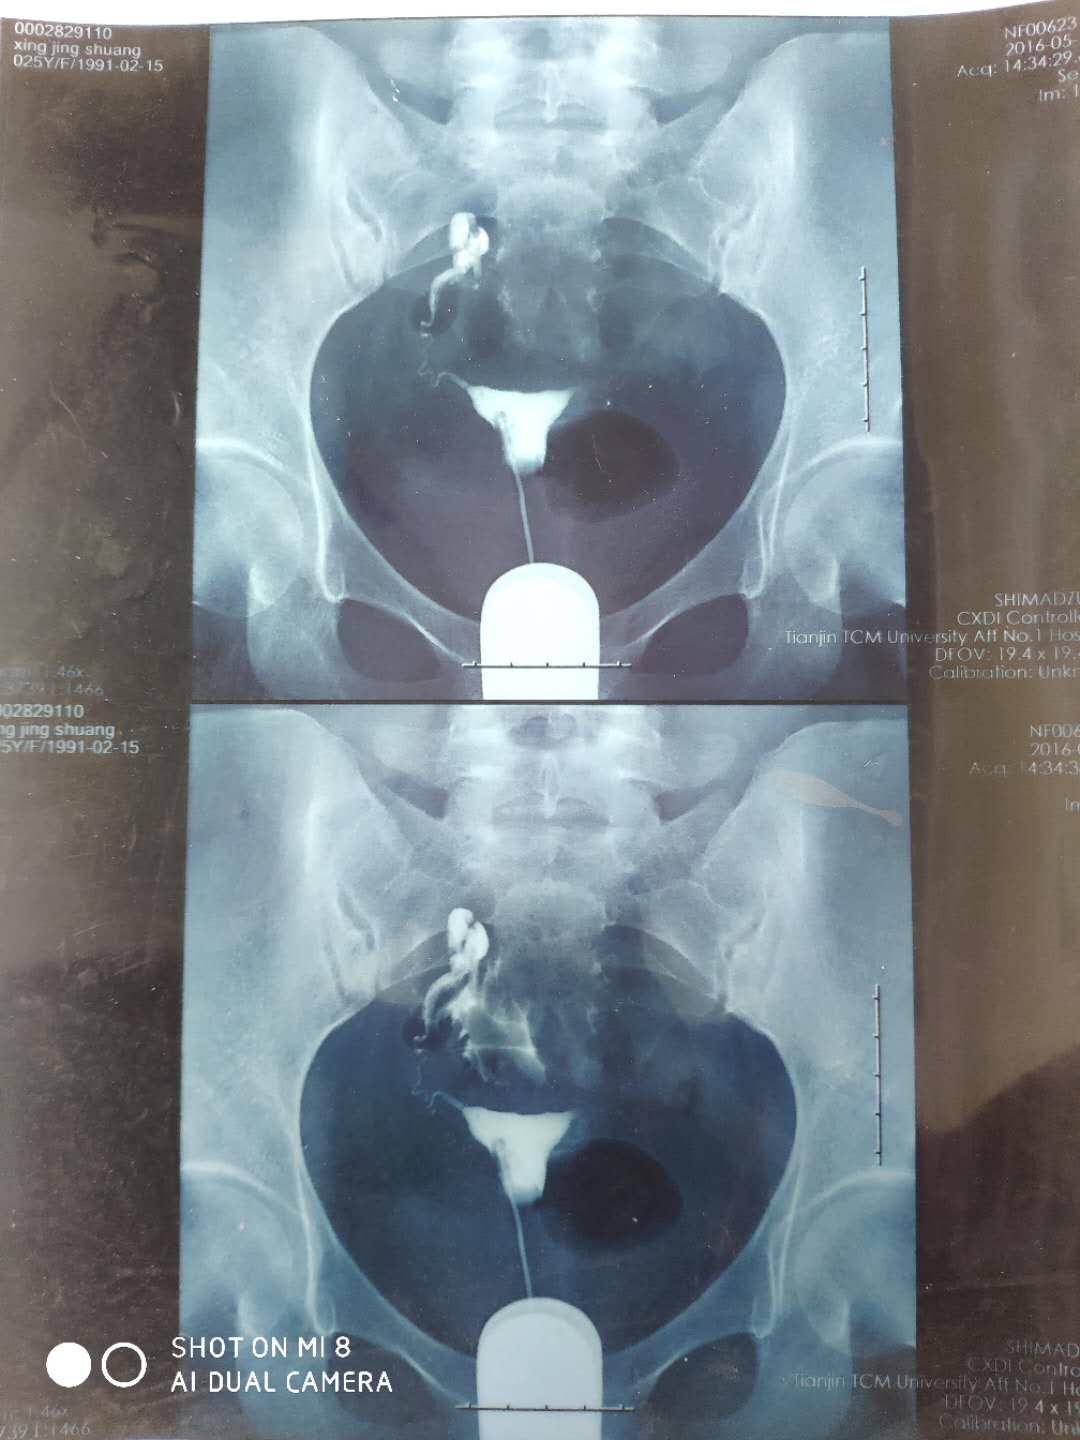

这种必须做手术么还是取了胚胎不是非要做

这个手术不是非得要马上做,需要根据你的年龄、生育计划等来综合评估并权衡利弊后再决定是否需要手术以及什么时候做。如果是做试管通常为了避免输卵管积液及炎症因子逆流至宫腔影响胚胎着床等,会行输卵管结扎等手术,这个手术通常在移植前完成